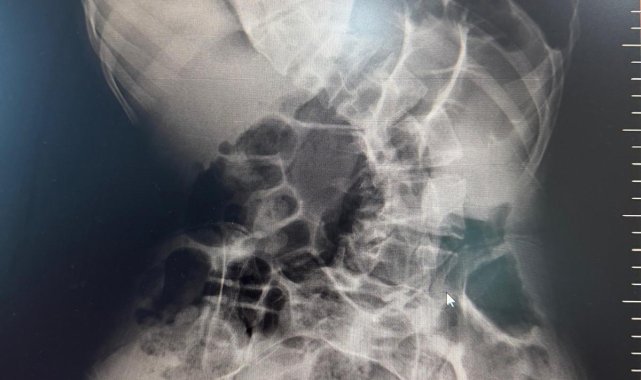

Kırgızistan'da 18 yaşına kadar skolyozla mücadele eden genç, Medicana Hastanesi'nde geçirdiği başarılı ameliyatın ardından sağlığına büyük ölçüde kavuştu.Skolyoz hastalığıyla mücadele eden 19 yaşındaki Shakhbos Pochokalonov, tedavi olmak için ülkesi Kırgızistan'dan Türkiye'ye geldi. Yaklaşık bir sene önce Ankara'ya gelen Pochokalonov, burada Medicana hastanesine başvurarak, tedavi sürecini başlattı. Pochokalonov, Medicana Sağlık Grubu bünyesindeki hastanede gerçekleştirilen operasyonla sağlığına kavuştu.Başarılı geçen ameliyat sonrası hastanın yaşam kalitesinin önemli ölçüde arttığını belirten Ortopedi ve Travmatoloji uzmanı Prof. Dr. Mehmet Atıf Erol Aksekili, skolyoz hakkında bilgi vererek, "Skolyoz kısaca omurganın S şeklini almasıdır. Ön-arka planda omurganın S şeklini almasını biz kısaca skolyoz diyoruz. Skolyoz en sık adolesan dediğimiz ergenlik döneminde görülür. Ancak diğer hastalıklarla birlikte görüldüğünde daha ileri seviyelerde karşımıza çıkabilir. Hastamız 18 yaşında bize başvurdu. Nöromüsküler skolyoz dediğimiz, nörolojik hastalıkların eşlik ettiği bir skolyoz tipi mevcut. Bu skolyozlar erken yaşta ortaya çıkar ve daha hızlı ilerler. Bu yüzden hastamız bize 90 dereceden daha ileri bir seviyede başvurdu" dedi."Erken teşhis tedaviyi kolaylaştırır"Erken teşhis edilmesi halinde daha az cerrahi ile daha iyi sonuç alınabileceğini belirten Aksekili, "Skolyoz erken tanındığında fizik tedavi, egzersiz ve korseleme gibi yöntemlerle ilerlemesini kontrol altına alabiliyoruz. Hastamızda ileri skolyoz olduğu için iki aşamalı cerrahi uygulandı. İlk aşamada Halo Femoral traksiyon yöntemiyle skolyoz kısmen düzeltildi. İkinci aşamada ise vidalar, rodlar ve osteotomi ile omurga düzeltildi" diye konuştu."Ameliyat sonrası süreç en az ameliyat kadar önemli"Ameliyat sonrası sürecin en az ameliyat kadar önemli olduğuna dikkati çeken Aksekili, omurganın uygun pozisyonda kaynamasının hedeflendiğini belirtti. Hastanın üç ay boyunca dorsolomber korse kullanması gerektiğini söyleyen Aksekili, "Yürümesi öneriliyor ancak ağır yük taşımaması gerekiyor. Yüzme gibi sporlara kısa sürede başlayabilir. Kaynama sürecinde diyetine dikkat etmeli ve 6 hafta ile 3 aylık periyotlarla kontrolleri yapılmalıdır. Kaynama istenilen şekilde ilerlemezse ek müdahaleler veya destek tedavileri uygulanabilir" açıklamasında bulundu."En yakın sağlık merkezine başvurulmalı"Erken teşhisin önemine vurgu yapan Aksekili, "Erken teşhis oldukça önemlidir. Nöromüsküler skolyozlar tamamen engellenemese de özellikle ergenlik dönemindeki skolyozlar uygun postür, egzersiz ve fiziksel aktivitelerle önlenebilir. Omuz ve kalça asimetrisi ya da öne eğilince kaburgada çıkıntı gibi belirtiler fark edildiğinde en yakın sağlık merkezine başvurulmalıdır" ifadelerini kullandı."Doktor öneriyorsa mutlaka ameliyat olunmalı"Baba İlhom Pochokalonov, ise oğlunun ilk teşhisini doğumundan bir yıl sonra fark ettiklerini belirterek, "18 yaşına kadar Kırgızistan'daki doktorlara gittik. Doğumsal skolyoz olduğunu, ameliyat olursa felç kalabileceğini söylediler. Skolyoz ile mücadele eden ailelere önerim, erken teşhis ve doğru zamanda ameliyat. Doktor öneriyorsa mutlaka ameliyat olunmalı. Biz Türkiye'ye geldik, ameliyat olduk ve şifa bulduk. Doktorlara çok minnettarız" ifadelerine yer verdi.